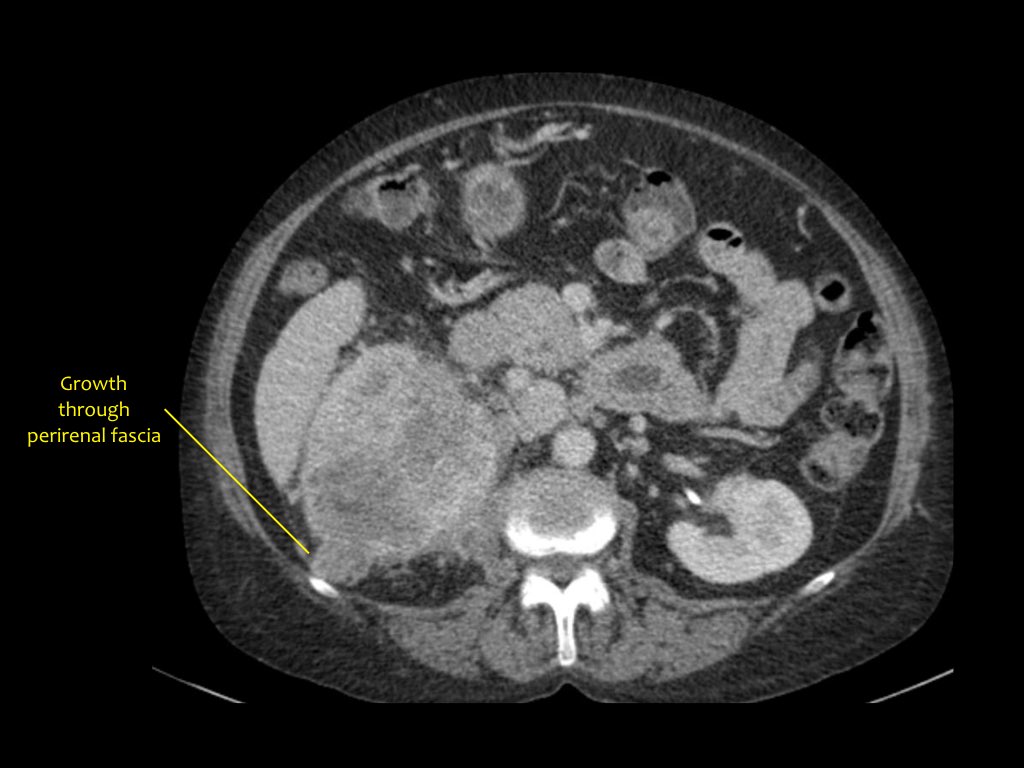

Phân giai đoạn RCC

RCC có thể xâm lấn mỡ quanh thận vượt qua cân thận và có thể lan vào tĩnh mạch thận, tĩnh mạch chủ dưới (IVC) hoặc tuyến thượng thận cùng bên.

Đối với phẫu thuật viên, điều quan trọng là cần biết có huyết khối u trong IVC hay không và liệu huyết khối có lan vào lồng ngực trên cơ hoành hay không (cần có phẫu thuật viên lồng ngực trong ca mổ).